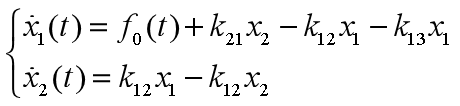

根据假设和图14所反映的关系,有如下模型 【4.1】

【4.1】

又根据血药浓度、房室容积、药物剂量的关系,有

【4.2】

【4.2】

将【4.2】代入【4.1】,有

【4.3】

【4.3】